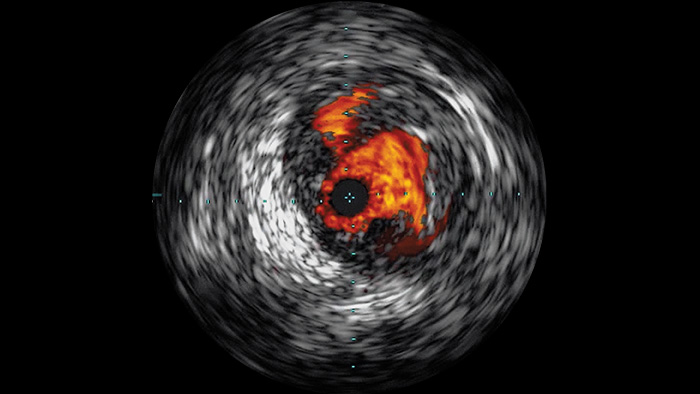

Der intravaskuläre Ultraschall (IVUS) ist eine katheterbasierte Bildgebungstechnologie, mit der Blutgefäße von innen nach außen dargestellt werden können, um das Vorliegen und das Ausmaß der Erkrankung zu beurteilen. IVUS unterstützt die Entscheidungsfindung, die Führung und die Bestätigung der richtigen interventionellen Behandlung für jeden einzelnen Patienten.

Hochauflösende Bilder von Gefäßen mit hervorragender Detailgenauigkeit zur Unterstützung durchdachter Behandlungsstrategien, präziser Navigation und Verlaufsbeobachtung